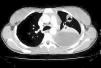

En la radiografía y tomografía axial computarizada (TAC) de tórax (figs. 1 y 2) se apreciaba una imagen redondeada y cavitada en lóbulo superior izquierdo, con un extenso derrame pleural del mismo lado.

Figura 2. Tomografía axial computarizada (TAC) pulmonar: se observa colección pleural izquierda con engrosamiento pleural difuso que ocasiona atelectasia del parénquima pulmonar adyacente. Nódulo cavitado con pequeño nivel hidroaéreo en lóbulo superior izquierdo.